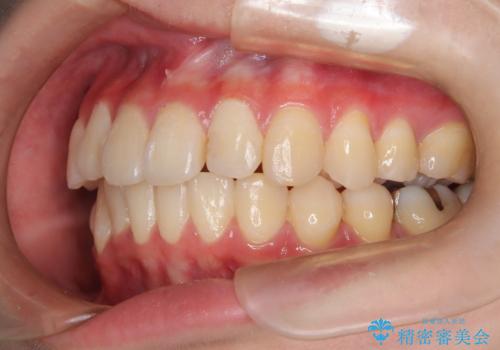

- 上下の前歯に捻れ(捻転)とガタつき(叢生)が見られます。

上の2番目の前歯の捻れに関しては、元々歯の大きさが小さい歯であるため、マウスピースにて力がかかりにくく、捻転の改善が一般的に難しくなりがちです。

下の犬歯に関しても捻れと傾き、ガタつきが大きく、歯根の長さも相まって移動の難易度が高くなりがちです。

インビザラインのそうした特色を踏まえた上で、それらをリカバーできるように治療方式の調整を十分に行い、治療を進めました。

マウスピース枚数 初回33枚 +追加22枚 +追加31枚

概ね2年で治療完了しました。

マウスピース矯正の特性として動かすのが難しい歯を含むケースでしたが、当院独自の工夫を随所に盛り込み、狙い通りの治療結果が得られました。